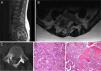

El paciente C tenía 15 años en el momento del diagnóstico. La clínica inicial fue dolor lumbar de unos 6 meses de evolución, en la RMN se evidenció una masa en apófisis espinosa de L4 que protruye a canal medular, sugerente de osteoblastoma (fig. 5). Se realizó una laminectomía descompresiva asociada a biopsia diagnóstica, confirmando en la anatomía patológica el diagnóstico inicial de osteoblastoma. El paciente presentó una mejoría clínica significativa. Al año de la cirugía es remitido a nuestro centro por dolor lumbar, realizándose una RMN, TC y gammagrafía ósea. Ante la sospecha de una recidiva tumoral, se realiza nueva biopsia, confirmando una recidiva de osteoblastoma. Por la agresividad local de la lesión se decide realizar mediante abordaje posterior, fijación L3-L5 y hemicorpectomía L4, tras disección marginal separando la masa de partes blandas posterior del saco dural hasta localizar la salida de las raíces L4 y L5. Se realizó resección con margen amplio de la parte lateral del cuerpo vertebral de L4 hasta llegar a cara anterior del cuerpo vertebral, colocando una valva maleable. Una vez disecada la cara lateral del cuerpo de L4 y separada la masa de partes blandas posterior se separó el saco dural hacia medial, siendo en este paso necesario realizar una resección completa-intralesional alrededor de la raíz de L5, con el objetivo de salvarla. Se realizó un corte en el disco superior e inferior, y posteriormente osteotomía longitudinal y oblicua desde posterior a anterior y hacia el lado derecho para obtener más margen del cuerpo vertebral. Una vez liberada la pieza se volteó hacia lateral, extrayendo el hemicuerpo, realizando una resección completa intralesional, con posterior reconstrucción mediante aloinjerto tricortical de cresta iliaca en el defecto anterior, llevando a cabo una fusión L3-L5 (fig. 6). La anatomía patológica de la muestra extraída fue diagnosticada de osteosarcoma vertebral en L4, Broders II, Enneking IIB, WBB ABCDE 11-5 y Tomita tipo 4. Tras los nuevos hallazgos, el paciente recibió tanto quimioterapia adyuvante como radioterapia local, se realizaron los controles pertinentes con radiología simple de la zona intervenida así como el protocolo de seguimiento oncológico. El paciente mejoró significativamente de la clínica inicial lumbar y ha permanecido hasta el momento actual libre de enfermedad.

Paciente C. A) Imagen de la pieza quirúrgica de la última cirugía, en la que se observa proliferación de células osteoblásticas, con algunas zonas más hipercelulares y con atipia, compatible con osteosarcoma simulador de osteoblastoma. B y C) Resultado posquirúrgico: hemicorpectomía L4+fijación posterior.